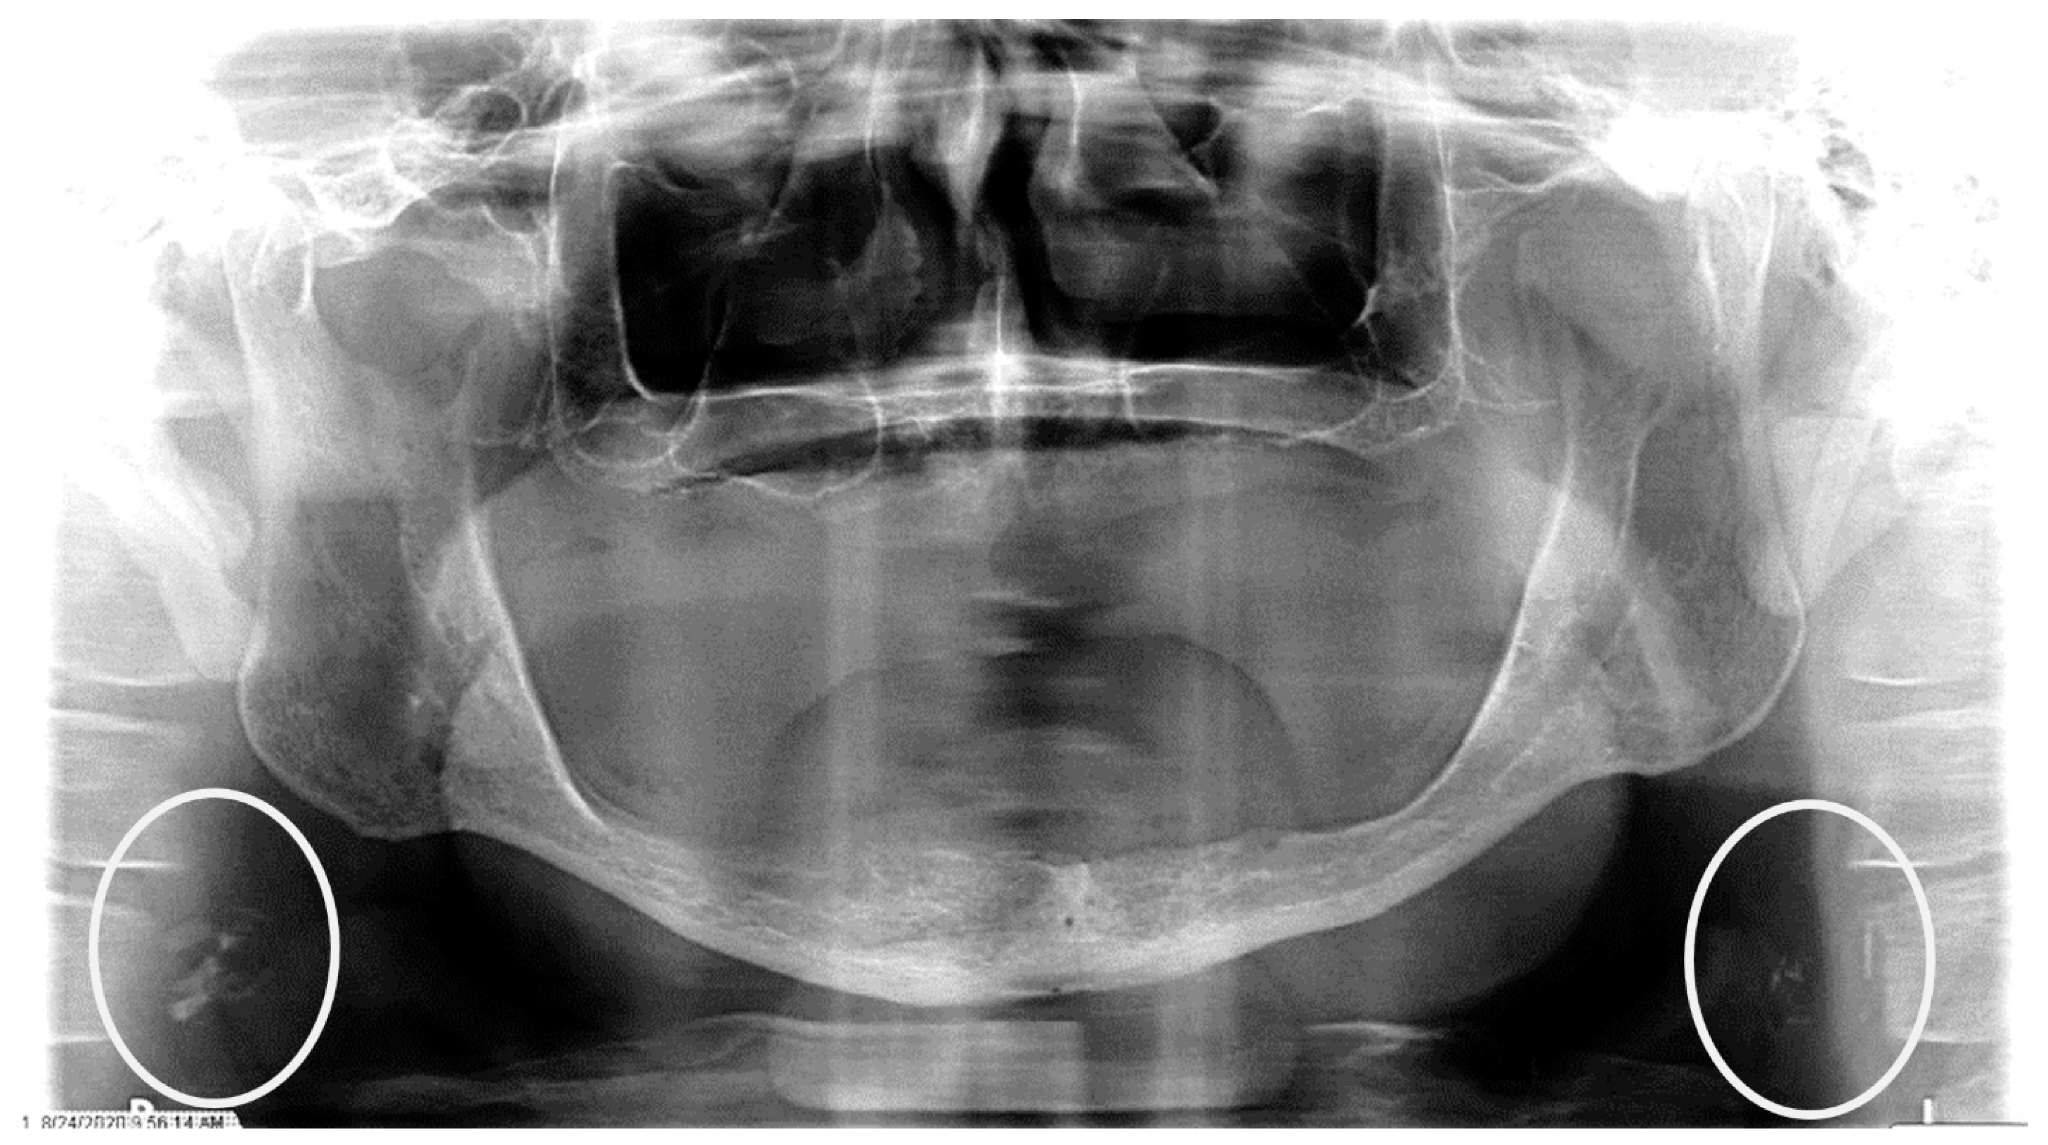

4. What condition can be seen in the following X ray?